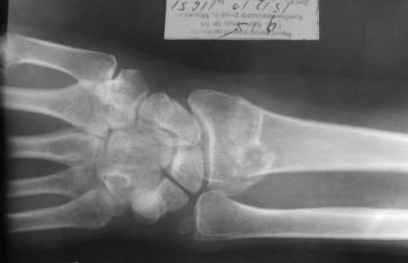

Уважаемые коллеги.Прошу обсудить случай лечения перелома дистального метаэпифиза лучевой кости. Ситуация скандальная и крайне неблагоприятная. Больная с патологической обстоятельностью мышления, склонностью к сутяжничеству, патологическими умозаключениями, не поддающимися коррекции (см. психиатрию, правда офиц. диагноза нет). В данном случае есть ряд ошибок с нашей стороны, прежде всего в отношении качества ведения документации (за что получил административное взыскание, по делом мне дураку). В остальном- придерживались в лечении подхода классический советской школы. Так как умную операцию…… сами знаете… 15.12- перелом луча в Москве. Там же репозиция, гипс. Дальнейшее лечение у нас в ЦРБ. 20.12.- вторичное смещение в гипсе21.12- под внутривенным наркозом- репозиция, гипсовая лонгета. Дальше начинается самое интересное. После репозиции больная заявила, что я (репозицию делал я) порвал ей все связки в суставе, посинел у нее 5 палец, якобы я за него тянул и т. д. На самом деле на 2 сутки после репозиции рука немного отекла и было незначительное сдавление гипсом, который был ослаблен. Дальнейшее лечение консервативное. Через 6 недель- гипс снят, назначено ЛФК. Пациентка крайне недовольна. Говорит, что на снимке у нее выступает кость, я ей сломал руку и.т.д. В общем началось. Пациентка прочитала в интернете наверное все, что есть по данной травме.По заключениями рентгенологов и консультанта из КДЦ областной больницы - стояние отломков допустимое. Объективно говоря- снижена высота лучевой кости, диастаз лучелоктевого сочленения, и не сросся шиловидный отросток. однако на РКТ при сравнении с другой стороной- разница незначительная. Дальше в одной из больниц нашей области и одной из больниц Москвы (вроде бы КГБ 53) врачи сказали, что репозиция сделана плохо. Нужна операция (восстановить длину лучевой кости), даже один из них предложил РЕДРЕССАЦИЮ (хи-хи) с наложением аппарата Илизарова. Что это для данной больной- радость неописанная. (см. описание психического статуса). Ничем другим, кроме зарабатывания дешевого авторитета объяснить данный факт не могу.Кстати, у больной еще нейропатия локтевого нерва.Для разрешения конфликта больная направлена на консультацию в ЦИТО на 03.03.11.

Теперь вопросы: 1.Прошу объективно оценить качество нашей репозиции на момент 21.12. (неужели так плохо?). Что на снимках при снятии гипса- сам вижу. 2. сравнить снимки РКТ (с двух сторон)- так ли велико укорочение лучевой кости и лучелоктевой диастаз. 3. Ваши мнения, в отношении целесообразности оперативного лечения учитывая ВСЕ вышеизложенное. 4. На всякий случай для суда- мог ли я тракцией в 2- 3 кг за 1 и 2 пальцы под внутривенным наркозом неправильно вколотить отломки и травмировать локтевой нерв. Кстати, в США если врач пациенту говорит, что его плохо лечили- то этого врача лишают лицензии. У нас наооборот- обгадить другого милое дело. И это процветает. От себя же могу сказать, что никто в нашем отделении так не поступает. Коллеги, будьте осторожны в своих высказываниях. От осложнений и ошибок никто не застрахован. А в данном случае многое будет зависеть от заключения консультантов поликлиники ЦИТО, куда больная направлена областным травматологом на 03.03 для решения вопроса о дальнейшей тактики лечения. С уважением ко всему травматологическому сообществу Дедок Михаил.

1. РЕПОЗИЦИЯ сделана качественно(ОСНОВНЫЕ 2 УГЛА ВЫСТАВЛЕНЫ ПРАВИЛЬНО ) , но перелом нестабильный и склонен к втор смещению . Поэтому мы стараемся все переломы со смещением фиксировать 3-МЯ спицами по GRIN методике .

1. Репозиция от 21.12.10 была выполнена лучше, чем первичная.